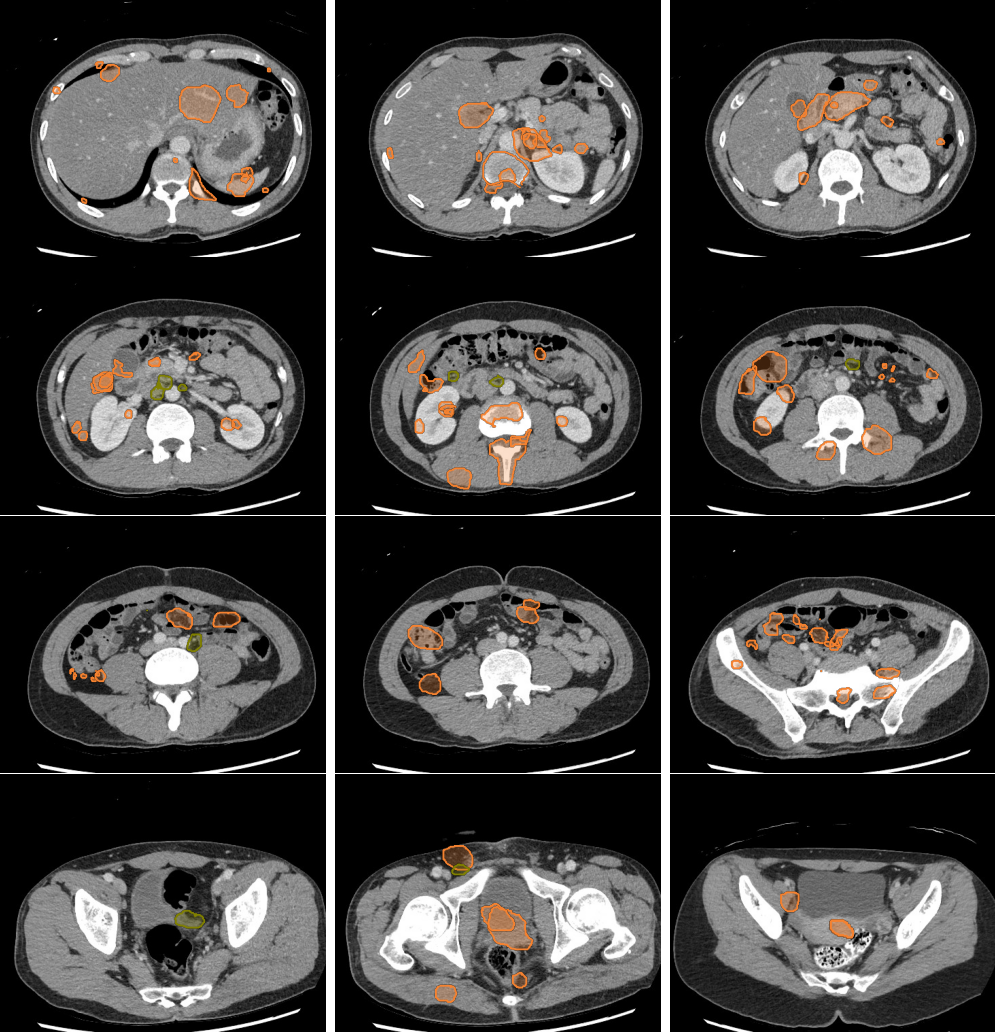

- Liver lesions can be subtle. Use a "Liver" window to increase sensitivity.

- Masses in the mesentery/peritoneum are often overlooked. Take advantage of multiplanar imaging and look in characteristic locations for peritoneal lesions.

- Kidney masses are also overlooked. Look carefully at the collecting system and for renal contour abnormalities.

Mass or Adenopathy

Slice 1

Slice 2

Slice 3

Slice 4

Slice 5

Slice 6

Slice 7

Slice 8

Slice 9

Slice 10

Slice 11

Slice 12